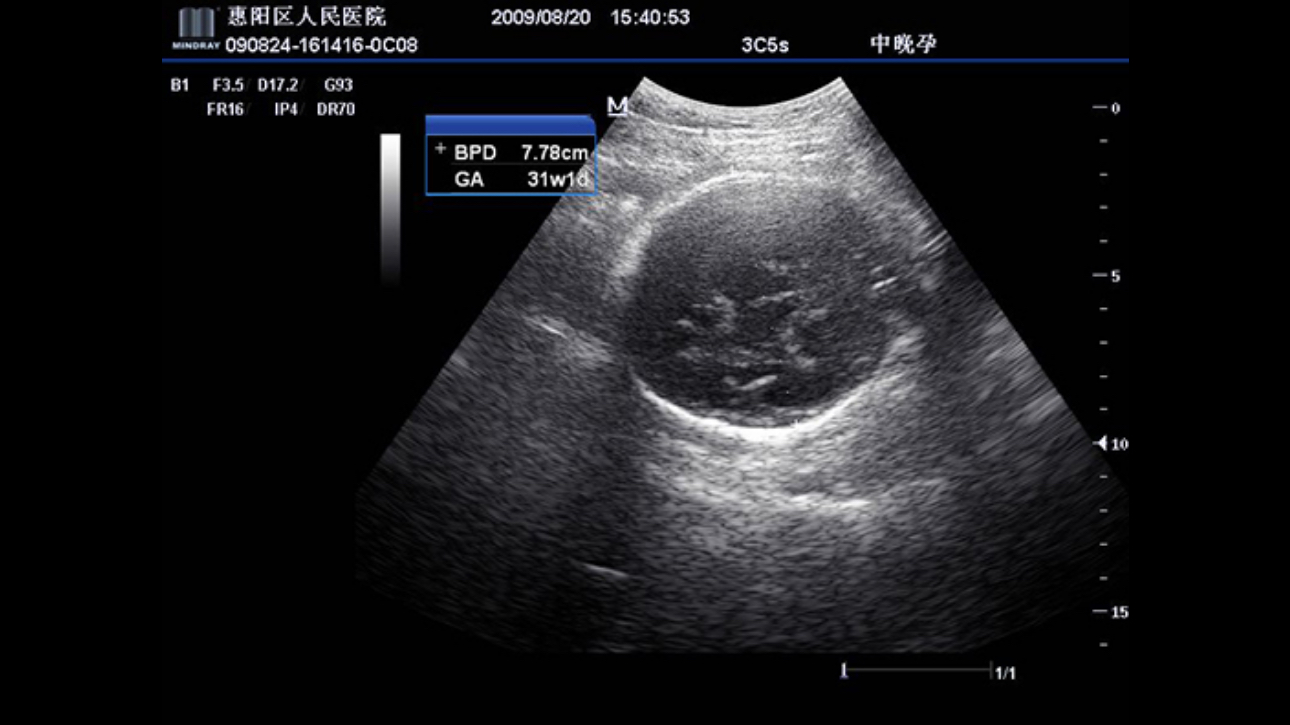

A fully-featured laptop style color Doppler system, M5 offers uncompromised 2D performance and exceptional value in a highly convenient and easy to use package. The portable, simplistic nature of the M5 makes it ideal for a variety of hospital and office environments.

PSHITM (Phase Shift Harmonic Imaging)

Purified Harmonic Imaging for better contrast resolution providing clearer images with excellent resolution and less noise.

Permits use of multiple scanned angles to form a single image, resulting in enhanced contrast resolution and improved visualization.

iClearTM (Speckle Suppression Imaging)

Gain improved image quality based on auto structure detection.

- Sharper & Continuous Edges

- Smooth Uniform Tissues

- Cleaner вАШno echo areasвАЩ